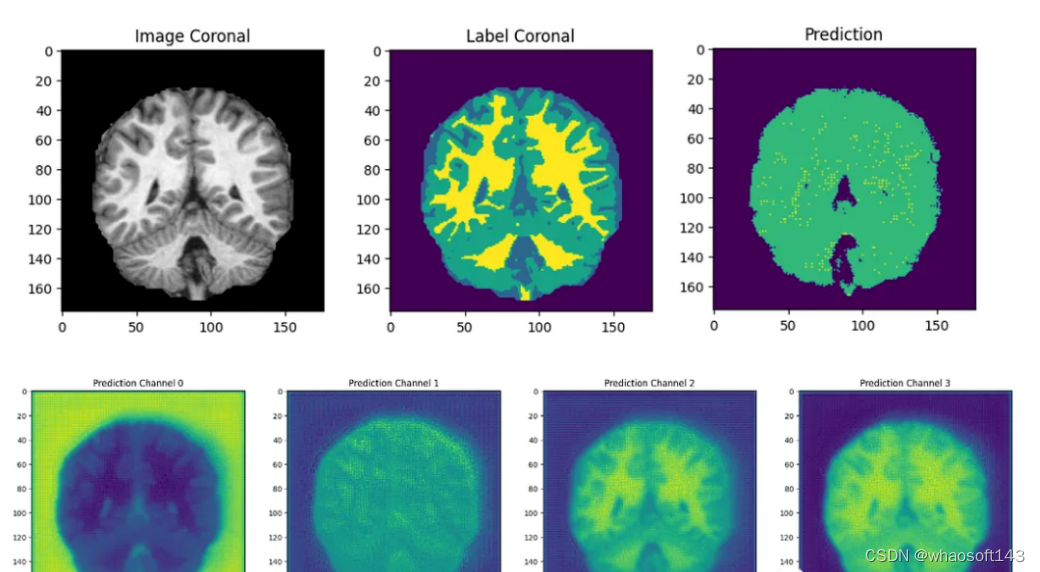

结果分析

最后我们要看看模型是如何推广到未知数据的这个模型预测的几乎所有东西都是左脑白质,一些像素是左脑皮层。尽管它的预测似乎是正确的,但仍有很大的改进空间,因为我们的模型太小了,可以选择更深的模型获得更好的效果。